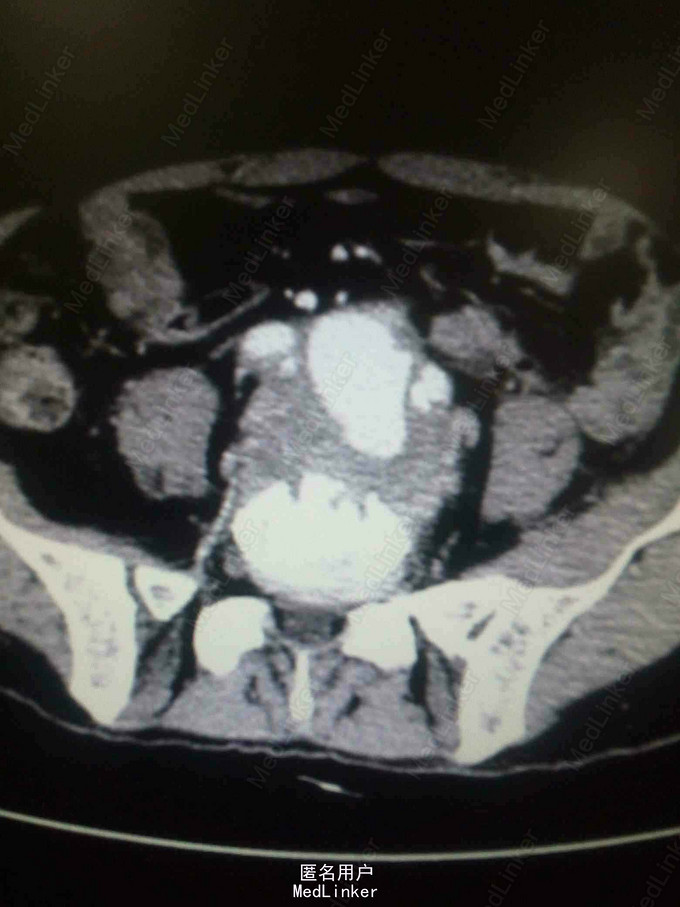

主诉:腰腹痛7月,加重一周。 病史:七月前发热后开始出现腰腹痛,呈持续性撕裂样痛,伴腹胀,症状反复。一周前腹痛症状加重。

体查:下腹部可触及搏动性包块。 辅助检查:腹部CT:腹主动脉假性动脉瘤并血栓形成,腰5椎体受侵蚀。血培养:沙门氏菌。

诊断:沙门氏菌感染性腹主动脉假性动脉瘤 处理:急诊行腹主动脉瘤切除人工血管置换术,术后予美罗培南抗感染8周,续以左氧氟沙星口服。